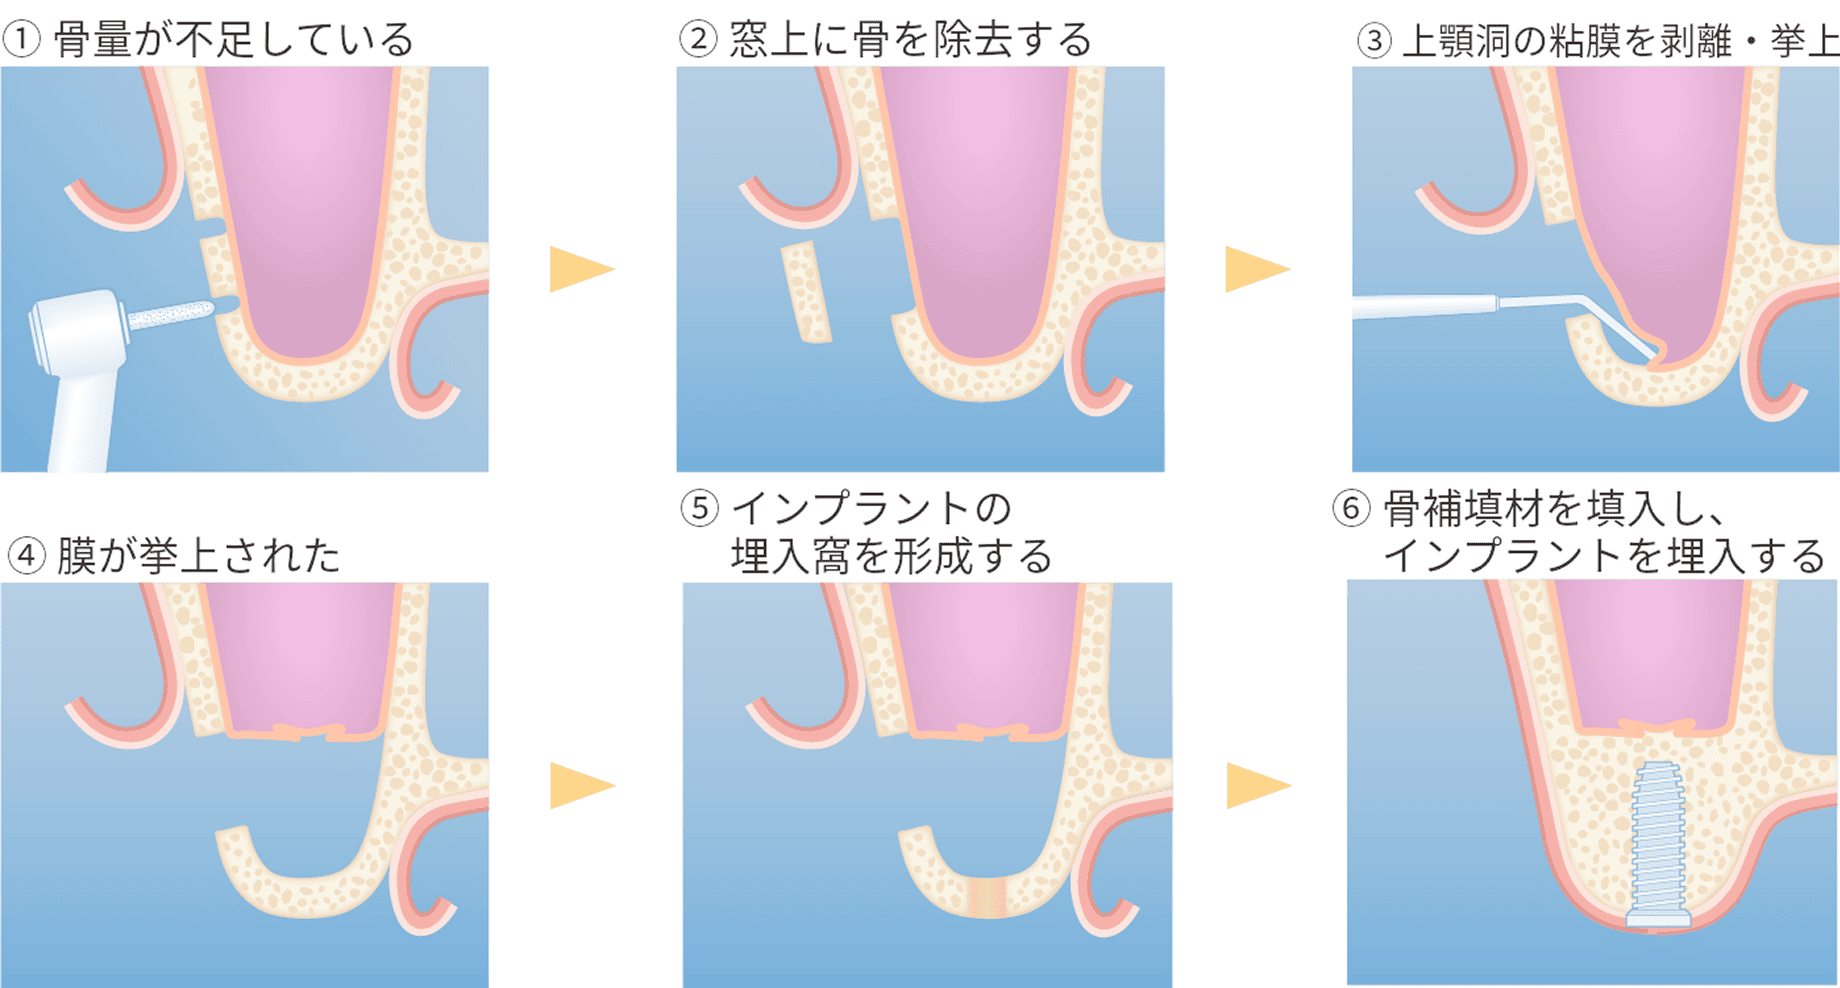

また、上顎奥歯など骨が特に薄い部位には「サイナスリフト(上顎洞底挙上術)」が適応されます。上顎洞と呼ばれる空洞の底を持ち上げ、その下に骨を造成することで、十分なインプラント埋入スペースを確保することが可能になります。